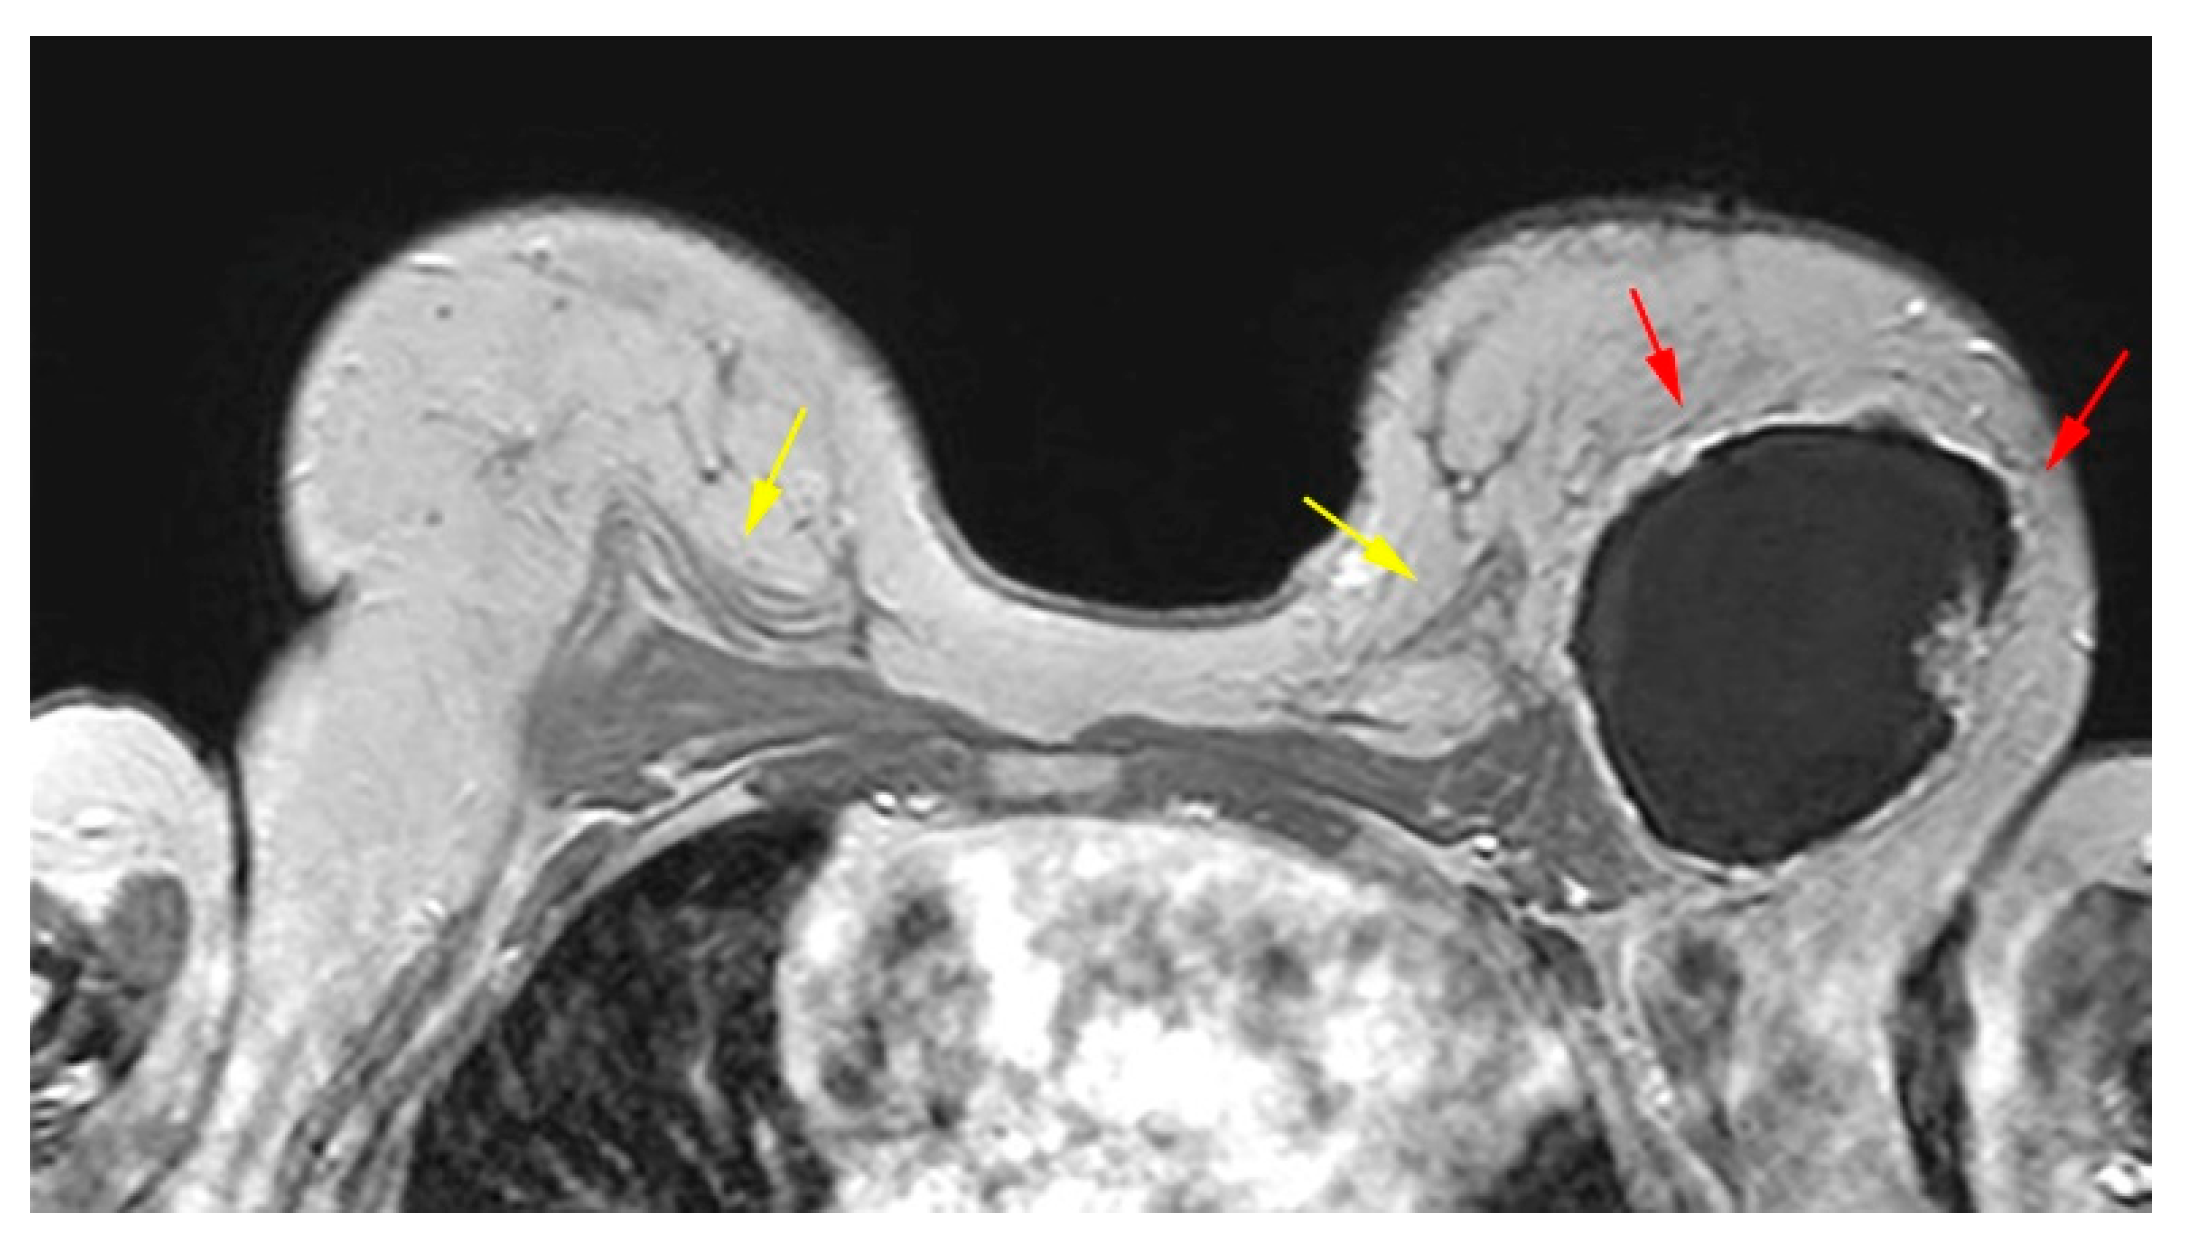

The pedicled or free TRAM flap and the LD flap consist of the rectus abdominis and latissimus dorsi muscle respectively and also the overlying skin and subcutaneous fat. In the TRAM reconstruction the flap is recognized centrally along the anterior chest wall in axial images. In the LD reconstruction the flap is more eccentric with a tailed appearance of the muscle in the lateral breast as a result of the flipping and tunneling of the flap harvested from the back, differentiating it from a TRAM flap (Figure 2) [35]. In both cases the muscle atrophies over time. A thin low signal intensity curvilinear line parallel to the breast contour is often visible, best appreciated on sagittal images, representing the dermal layer of the lower abdominal or the dorsal wall [35,45]. The contact zone of the TRAM flap to the mastectomy site, that corresponds to the musculovascular pedicle may exhibit contrast enhancement [46].

Figure 2. Bilateral autologous Latissimus Dorsi (LD) reconstruction. Yellow arrows point the characteristic tailed aspect of the muscle. Red arrows depict a hypointense circumscribed area with irregular wall enhancement and associated solid enhancing nodule corresponding to a local relapse of high grade invasive ductal carcinoma, triple negative, with marked central necrosis.